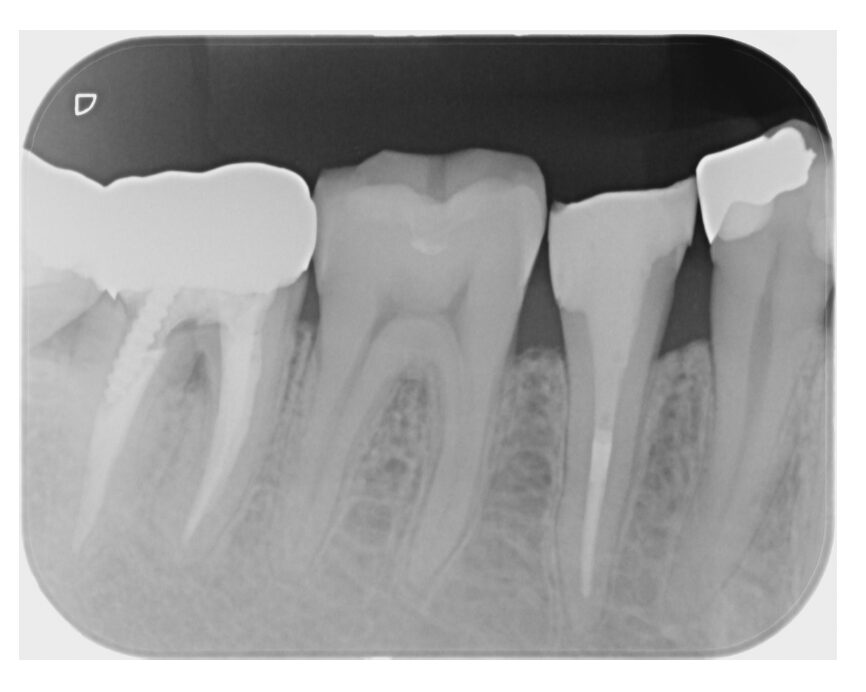

銀歯の下での虫歯の再発に対し、根管治療を歯内療法の専門医と連携しやり直し(自由診療)、その後セラミックで補綴処置を行なった。

まず根管治療において、保険診療の成功率は一般的に30〜50%程度(再治療の場合はさらに低下)と言われますが、専門医がマイクロスコープやラバーダムを用いて行う精密治療では、成功率が60〜90%近くまで向上します。肉眼では見えない汚れを徹底的に除去し、隙間なく密閉することで、数年後の「再感染による抜歯」のリスクを最小限に抑えています。

| 銀歯の下での虫歯の再発に対し、根管治療を歯内療法の専門医と連携しやり直し(自由診療)、その後セラミックで補綴処置を行なった。 |